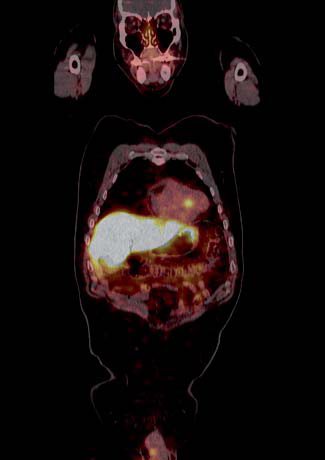

Tumores gastroenteropancreáticos

Este grupo (GEP) constituyen un grupo heterogéneo de tumores neuroendocrinos del estómago, páncreas e intestino. El más frecuente es el tumor carcinoide. El tratamiento primario es la cirugía aún en los pacientes con enfermedad metastásica, debido a que la resección parcial puede mejorar la calidad de vida, sobrevida y estado funcional. Las imágenes cumplen un papel importante para determinar la extensión de la enfermedad al inicio y en el seguimiento. Los estudios realizados con 111In pentatreotide muestran elevada sensibilidad para la detección de GEP a excepción del insulinoma. La sensibilidad para el gastrinoma metastásico, carcinoide y otros GEP son generalmente sobre 80% hasta 94%. La sensibilidad para la enfermedad metastásica tiende a ser superior a la de los tumores primarios (Figura 1) y en muchas ocasiones se encuentran lesiones no detectables por imágenes anatómicas. Utilizando Ga68 análogos de somatostatina se han obtenido excelentes resultados, con sensibilidades entre 82-100% (Figuras 2 y 3). El FDG tiene baja sensibilidad para la detección de estos tumores de lento crecimiento, bien diferenciados y bajo Ki-67, en cambio las imágenes con análogos de somatostatina presentan un patrón opuesto (Figura 4 y 5). Los tumores neuroendocrinos indiferenciados y agresivos presentan marcada avidez por la glucosa y pobre expresión de receptores de somatostatina y viceversa. Se ha visto que los pacientes con tumores con mayor expresión de Ki-67 evolucionan peor que aquellos con bajo Ki-6715. Los tumores neuroendocrinos que captan FDG tienen por lo tanto peor pronóstico16. En un estudio que comparó el rendimiento de cintigrafía con Octreoscan y FDG en pacientes con tumor carcinoide encontró que el 86% de los tumores primarios se localizaban con pentatreotide mientras que sólo el 57% con FDG. Pacientes con metástasis, el 69% fue positivo con el análogo de somatostatina, 47% con FDG y 56% con imágenes anatómicas17. Figuras similares se han obtenido con el uso de PET y Ga68análogos de somatostatina18,19.